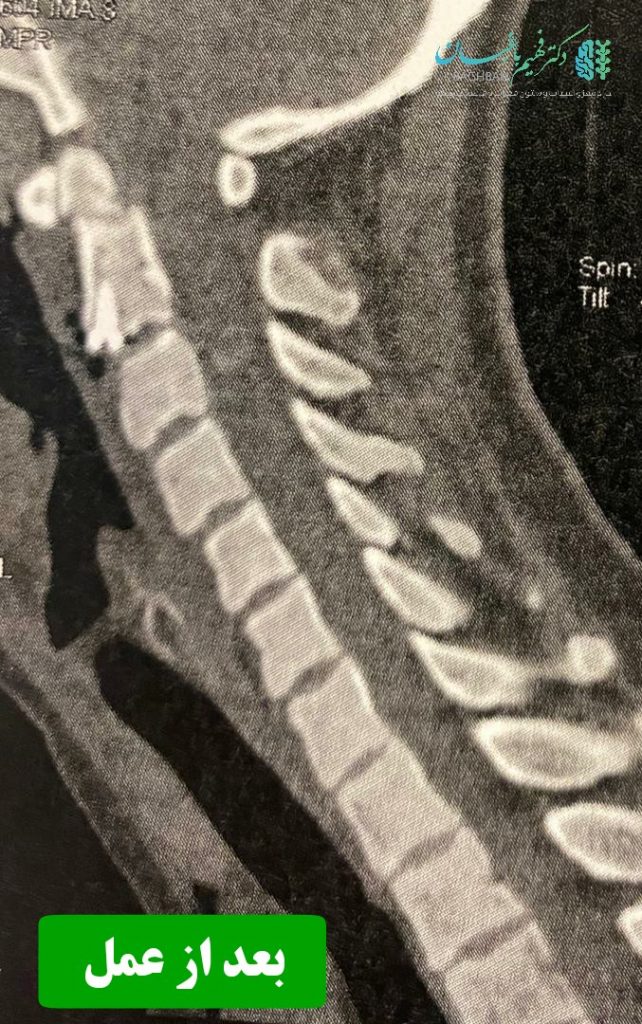

بیمار خانم جوان با سابقه ضربه شدید گردن و شکستگی زائده ادونتویید مهره دوم گردن که تحت عمل جراحی قرار گرفتند. تصاویر قبل و بعد از عمل را در زیر مشاهده می نمایید . همچنین توضیحات دکتر باغبان را در حین جراحی در ویدئوی انتهای مقالات مشاهده کنید. (ویدئو حاوی تصاویر جراحی می باشد)

تصاویر بعد از عمل